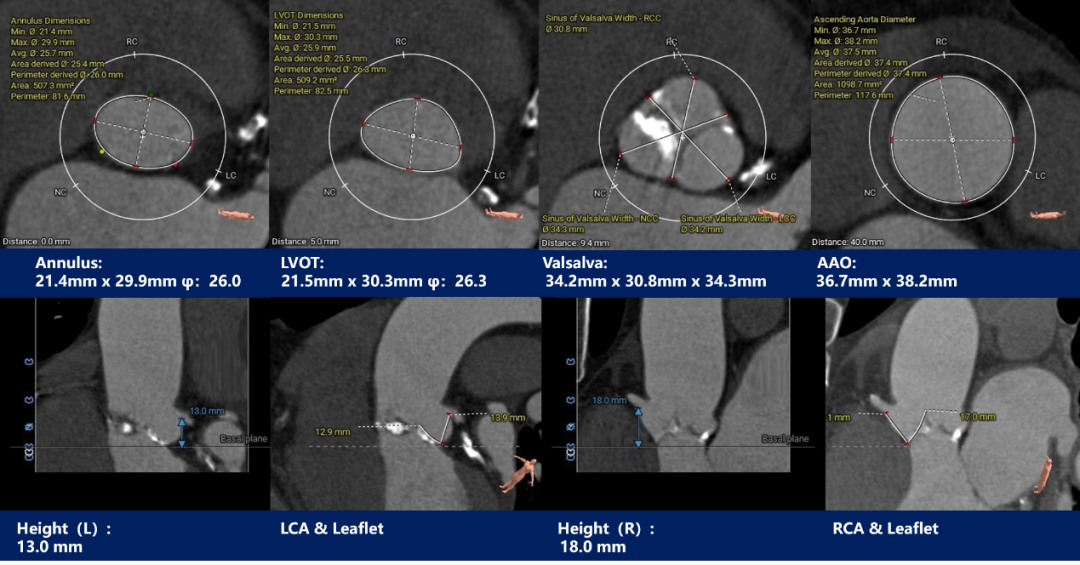

瓣上测量

流入端呈敞口形态,STJ、瓦氏窦内径、升主动脉内径可,主动脉瓣环与水平面夹角51度,非横位心;主动脉弓部夹角与弓距可,应用TaurusElite输送器可顺利过弓、跨瓣;

因患者为三叶瓣且钙化基本分布在瓣叶上,决定不进行球囊预扩张;依据瓣环及瓣上测量结果,预装TaurusEliteAV26瓣膜,左右重合体位零位起始释放,结合正交体位进一步明确瓣膜植入深度,视情况决定是否后扩;